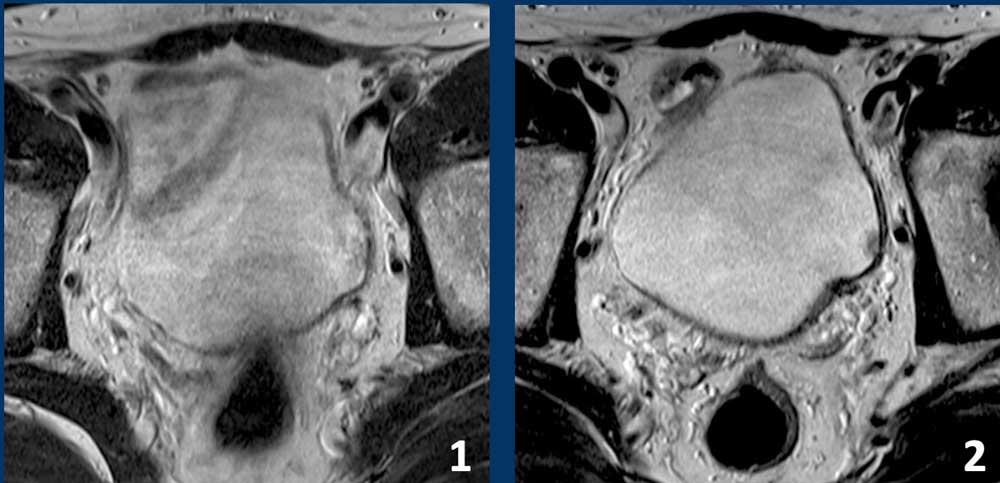

Độ căng bàng quang

Độ căng bàng quang tối ưu đóng vai trò then chốt trong việc phân giai đoạn khối u chính xác.

Tất cả các hình ảnh dưới đây đều là bàng quang bình thường.

- Căng không đủ

thành bàng quang có hình ảnh dày và không đều, có thể dẫn đến chẩn đoán nhầm hoặc đánh giá quá mức giai đoạn khối u. - Căng bàng quang đúng mức.

Hướng dẫn bệnh nhân đi tiểu trước khi chụp 1–2 giờ hoặc uống 500–1000 ml nước trong vòng 30 phút trước khi thực hiện thủ thuật, tùy theo khả năng dung nạp của bệnh nhân.

Hình dạng vòm bàng quang lồi ra ngoài gợi ý độ căng bàng quang tối ưu (2). - Căng quá mức.

Tình trạng này có thể gây xảo ảnh do chuyển động liên quan đến khó chịu và có thể che khuất mức độ lan rộng của ung thư bàng quang.